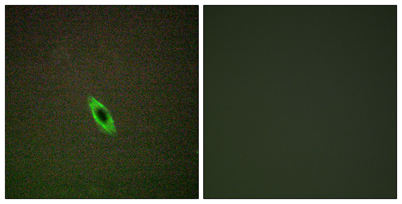

IF

Recomended Dilution Immunohistochemistry: 1/100 - 1/300. Immunofluorescence: 1/200 - 1/1000. ELISA: 1/5000. Not yet tested in other applications.